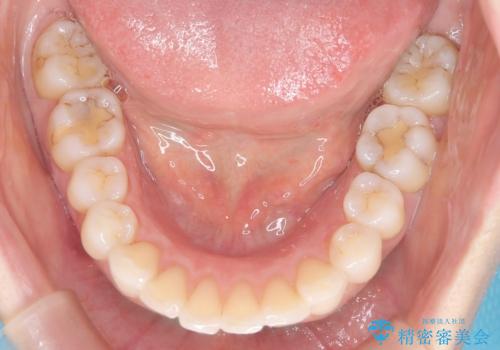

- 患者様は**歯の凸凹(叢生)**を気にされて来院されました。診査の結果、歯列のスペースが不足しているものの、抜歯をせずに改善できる状態でした。そこで、目立ちにくい審美装置(白いブラケットとホワイトワイヤー)を使用したワイヤー矯正を提案しました。歯列のアーチを広げながら、適宜IPR(歯の幅をわずかに調整する処置)を行い、非抜歯で自然な歯並びへと導く計画を立てました。

治療では、白いブラケットとホワイトワイヤーを使用し、矯正装置が目立ちにくいよう配慮しました。歯列を拡大しながら適切に歯を移動させ、IPRを併用することで、無理なくスペースを確保しました。見た目に配慮しながら、歯の凸凹をスムーズに整え、噛み合わせも改善。患者様からは「装置が思ったより目立たず、歯並びがきれいになって嬉しい」との声をいただきました。